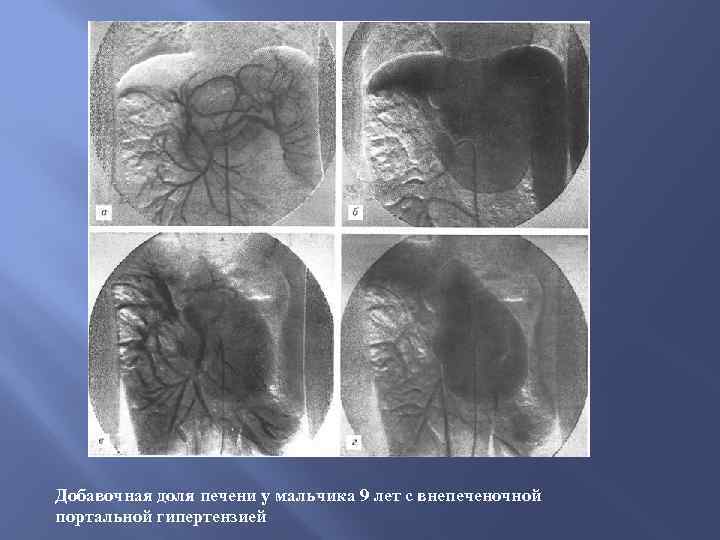

Добавочная доля печени у мальчика 9 лет с внепеченочной портальной гипертензией

Добавочная доля печени у мальчика 9 лет с внепеченочной портальной гипертензией